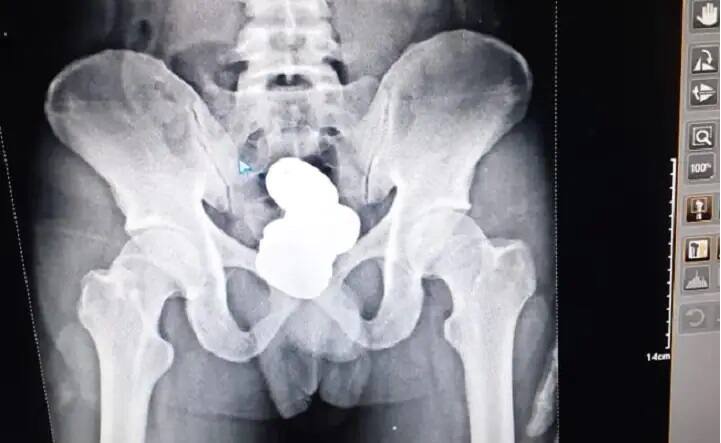

ਸੋਨੇ ਦੀਆਂ ਤਸਕਰੀ 'ਚ ਫੜਿਆ ਗਿਆ ਮੁਲਜ਼ਮ ਇੰਫਾਲ ਤੋਂ ਦਿੱਲੀ ਜਾਣ ਵਾਲਾ ਸੀ। ਉਸ ਨੇ ਕਰੀਬ 900 ਗ੍ਰਾਮ ਵਜ਼ਨ ਦਾ ਸੋਨੇ ਦਾ ਪੇਸਟ ਆਪਣੇ ਪੇਟ ਦੇ ਗੁੱਦੇ 'ਚ ਲੁਕਾਇਆ ਸੀ। ਜਾਂਚ ਤੋਂ ਬਾਅਦ ਪੁਲਿਸ ਨੇ ਯਾਤਰੀ ਦੀ ਤਲਾਸ਼ੀ ਲਈ ਜਿਸ ਦੌਰਾਨ ਦੀ ਸੀਆਈਐਸਐਫ ਤੇ ਕਸਟਮ ਦੇ ਅਧਿਕਾਰੀਆਂ ਨੂੰ ਉਸ ਦੇ ਗੁੱਦੇ 'ਚ ਕਰੀਬ 908.68 ਗ੍ਰਾਮ ਦੇ ਵਜ਼ਨ ਦੇ ਗੋਲਡ ਦੇ ਚਾਰ ਪੈਕੇਟ ਦਿਖੇ।

ਐਕਸ-ਰੇਅ ਤੋਂ ਲੱਗਿਆ ਪਤਾ

ਇਸ ਤੋਂ ਬਾਅਦ ਅਧਿਕਾਰੀ ਉਸ ਦਾ ਮੈਡੀਕਲ ਕਰਨ ਲਈ ਲੈ ਗਏ ਜਿੱਥੇ ਉਸ ਦੇ ਸਰੀਰ ਦੇ ਹੇਠਲੇ ਹਿੱਸੇ ਦਾ ਐਕਸ-ਰੇਅ ਕੀਤਾ ਗਿਆ। ਐਕਸ-ਰੇਅ 'ਚ ਯਾਤਰੀ ਦੇ ਗੁੱਦੇ 'ਚ ਗੋਲਡ ਪੇਸਟ ਦੇਖ ਸਭ ਦੰਗ ਰਹਿ ਗਏ। ਗੋਲਡ ਪੇਸਟ ਦਾ ਪਤਾ ਲੱਗਣ ਤੋਂ ਬਾਅਦ ਯਾਤਰੀ ਨੇ ਆਪਣੇ ਇਲਜ਼ਾਮ ਕਬੂਲ ਕਰ ਲਏ। ਬਾਅਦ 'ਚ ਯਾਤਰੀ ਨੂੰ ਅੱਗੇ ਦੀ ਕਾਰਵਾਈ ਲਈ ਕਸਟਮ ਤੇ ਸੀਆਈਐਸਐਫ ਨੂੰ ਅੱਗੇ ਸੌਂਪ ਦਿੱਤਾ ਗਿਆ।